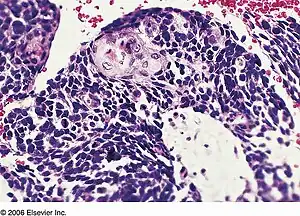

Combined small cell lung carcinoma containing a component of squamous cell carcinoma

a,b)Histopathology of combined small-cell lung cancer